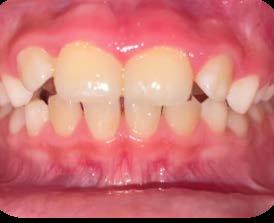

Sobremordida vertical excesiva en paciente pediátrico. Caso clínico

Entre los elementos que conforman al sistema estomatognático, están los dientes caninos, órganos dentales esenciales en la fisiología masticatoria; punto de unión y continuidad estética entre la línea de la sonrisa y el corredor posterior del arco dental, además de que ejercen la función de pilares estabilizadores en la oclusión fisiológica (Figura 1).

Los caninos son indispensables durante los movimientos de lateralidad y vitales para la continuidad de los arcos dentales, tanto en la dentición decidua como en la permanente; son responsables del funcionamiento y la armonía oclusal. Su posición adecuada en el arco asegura un buen contorno de la cara, sonrisa agradable y armónica con la estética facial. (Figura 2).